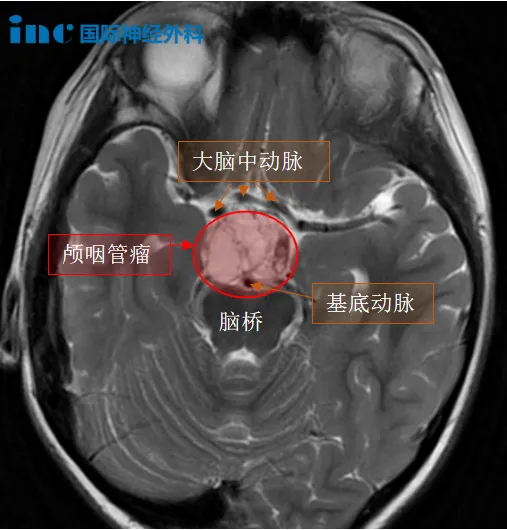

小迪罹患的是颅咽管瘤,血型是少见“熊猫血”。手术面临多重困难:

1、小迪的肿瘤恰好从垂体柄长出来,且对于有钙化(钙化就是俗话说的“石头”,有钙化就意味着肿瘤质地硬,切除困难,在切除时容易损伤周围血管和神经。)的颅咽管瘤来说,由于垂体柄较大限度地被肿瘤压扁,保留垂体柄更加困难。垂体柄是下丘脑跟垂体的联系通路,垂体柄断了会导致激素水平下降,还出现尿崩症,需要终生服药,巴教授的手术都避免了这些并发症。

3、病灶位于鞍区,鞍区解剖结构相当复杂,是颅内血管和神经较集中的区域之一。视交叉与视神经同鞍区有密切的相邻关系,使肿瘤的处理显得较为棘手。需保留这些结构也是巴教授手术的原则之一。

颅咽管瘤毗邻下丘脑和垂体,会对儿童的生长发育造成很大的影响,再加上位置深、手术难度大、复发率高,手术难度较大,围手术期并发症较多,患者预后较差。当脑瘤的魔爪伸向幼小的生命,恐惧、悲伤、绝望,这不仅是一个孩子的生命,更是整个家庭的未来。

颅咽管瘤图片